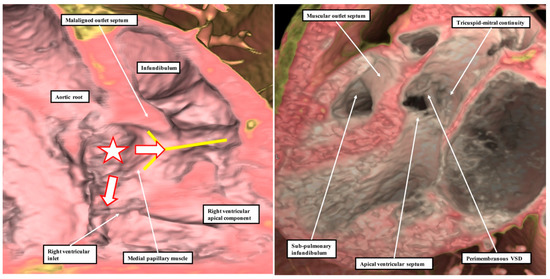

Poelmann and Gittenberger-de Groot [1] are correct in asserting that the so-called “aortopulmonary septal complex” is better termed the “outflow tract septal complex”. This fact is of particular importance for the understanding of postnatal anatomy and has significance for the categorisation of ventricular septal defects [3]. This is because when development proceeds normally, the entities which divide the developing outflow tract, and which initially have a septal location, subsequently lose this septal function. This occurs concomitantly with the development of the discrete walls of the intrapericardial arterial trunks, the separation of the aortic and pulmonary roots, and the formation of the free-standing muscular subpulmonary infundibulum. As suggested above, these findings have implications far beyond the understanding of normal postnatal anatomy. The fact that the proximal outflow cushions initially muscularise to produce a septum between the components of the proximal outflow tract, but that with normal development the muscularised tissues subsequently become the free-standing muscular subpulmonary infundibulum, is key to arbitrating ongoing discussions regarding the optimal means of categorising ventricular septal defects in the clinical setting [3]. Thus, the findings show that the notion that the normal muscular ventricular septum has a component derived from the “conus” has no developmental foundation. The same goes for the alleged “septum of the atrioventricular canal”. The definitive ventricular septum has only apical muscular and fibrous components, the fibrous part usually being described as the membranous septum. Our initial studies of the anatomy of ventricular septal defects had indicated that all could be categorised, according to the nature of their borders, into those abutting the remnants of the membranous septum, those embedded within the apical muscular septum, or those reflecting the lack of muscularisation of the proximal outflow cushions [12]. The findings as described by Poelmann and Gittenberger-de Groot [1] provide further evidence in support of this concept. They can be interpreted to endorse the notion that it is the borders of ventricular septal defects that serve best to define their phenotypic differences [13]. This is because it is not possible, when using geography as the starting point for categorisation, to show these crucial phenotypic differences. This potential deficiency of beginning categorisation on the basis of geography is well demonstrated by considering the defects that open to the inlet of the right ventricle (Figure 8).

Figure 2. These images show the findings subsequent to the dissection of normal hearts. The image in the left-hand panel shows the area of extracavitary adipose tissue that interposes between the posterior wall of the infundibulum, also known as the ventriculo-infundibular fold, and the aortic root. The yellow “Y” shows the septal band, or septomarginal trabeculation, with the medial papillary muscle, or papillary muscle of the conus, arising from its postero-caudal limb. The right-hand panel shows another heart in which the myocardial sleeve supporting the leaflets of the pulmonary valve has been sectioned, permitting the pulmonary root to be lifted away from the base of the ventricular mass (see also Figure 4C). The yellow “Y” again shows the location of the septal band. The dissections reveal the lack in the normal heart of a “muscular outlet septum”.